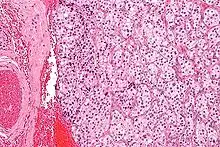

On microscopic inspection, the tumor cells are readily recognized. Individual tumor cells are polygonal to oval and are arranged in distinctive cell balls, called Zellballen.[8] These cell balls are separated by fibrovascular stroma and surrounded by sustentacular cells.

By light microscopy, the differential diagnosis includes related neuroendocrine tumors, such as carcinoid tumor, neuroendocrine carcinoma, and medullary carcinoma of the thyroid.

With immunohistochemistry, the chief cells located in the cell balls are positive for chromogranin, synaptophysin, neuron specific enolase, serotonin, neurofilament and Neural cell adhesion molecule; they are S-100 protein negative. The sustentacular cells are S-100 positive and focally positive for glial fibrillary acidic protein. By histochemistry, the paraganglioma cells are argyrophilic, periodic acid Schiff negative, mucicarmine negative, and argentaffin negative.

Micrograph of a carotid body tumor